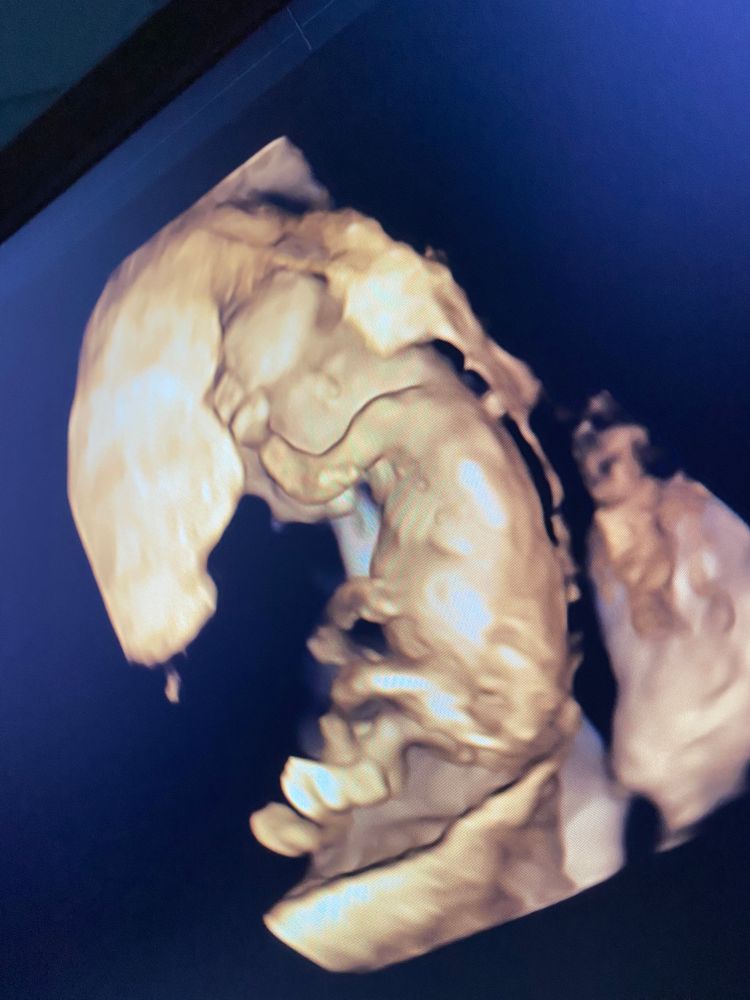

Чашка утреннего кофе, вот этот снимок где мне показали и сказали мальчик 100% . Это вид снизу ( попа и писюн)

Татьяна, дубль 2) в 13 недель, если плод не опережает развитие на пару недель, между ножек у мальчиков и девочек все совершенно одинаково выглядит. Разница только в угле наклона, это смотрят строго в профиль. Ракурс снизу между ножками информативен только после 15 недель. До этого там у девочек все то же самое. Да, пол часто предполагают правильно, но исходя из угла наклона.